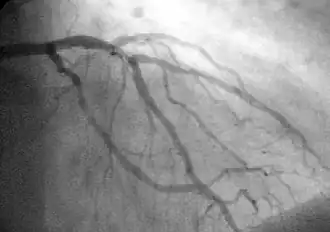

Coronary Angiography (CAG[3]).

Coronary angiography of a critical sub-occlusion of the common trunk of the left coronary artery and the circumflex artery. (See arrows)